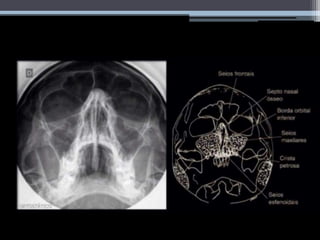

Radiografia Convencional

Perfil Axial de Hirtz

Mentonaso (Waters)

• #22 Seios maxilares, esfenoidais, células etmoidais, fossas nasais. Pirâmides petrosas visualizadas simetricamente.

• #27 Lembrar animação sobre a outra imagem Importante falar da drenagem: Ostio Recesso (parte superior e inferior) O grau de pneumatização varia e tem um efeito significante no tamanho no óstio frontal e na forma do recesso. Se a ANC for pequena, o processo frontal da maxila que se situa superior e anteriormente será proeminente, e vai-se estender posteriormente para o recesso frontal, resultando num óstio mais pequeninho. Pelo contrário, se a ANC é grande, o bico do processo será mais pequeno, resultando num óstio maior. Pathway – o compartimento superior do recesso é formado pela união das hemicélulas frontais e etmoidais. A margem superior é o óstio frontal. Comunica diretamente com o compartimento inferior, que é um canal mais estreito, formado pelo infundíbulo etmoidal ou pelo meato médio.